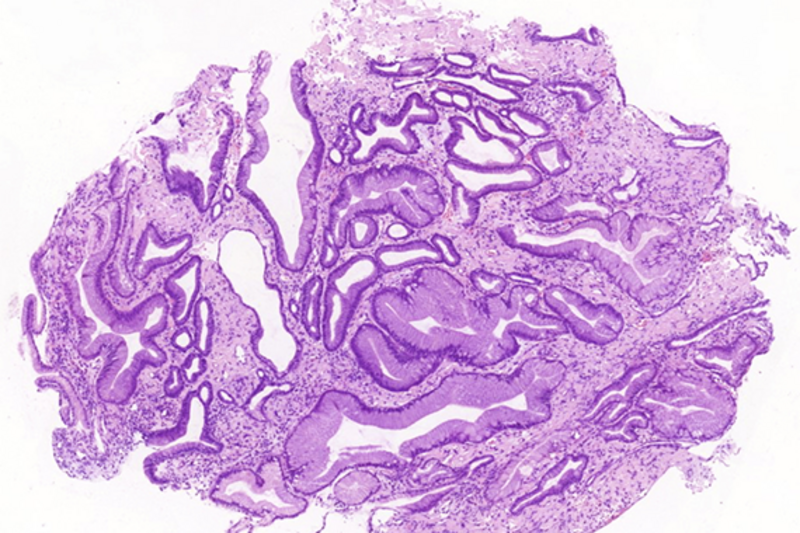

Due to recurrent gastrointestinal bleeding and significant involvement of the stomach with amyloidosis, a distal resection of stomach was performed. Histological findings (Panel E) in the resection specimen, including Congo Red stain (Panel F) were similar to those described in the pre-operative biopsy.